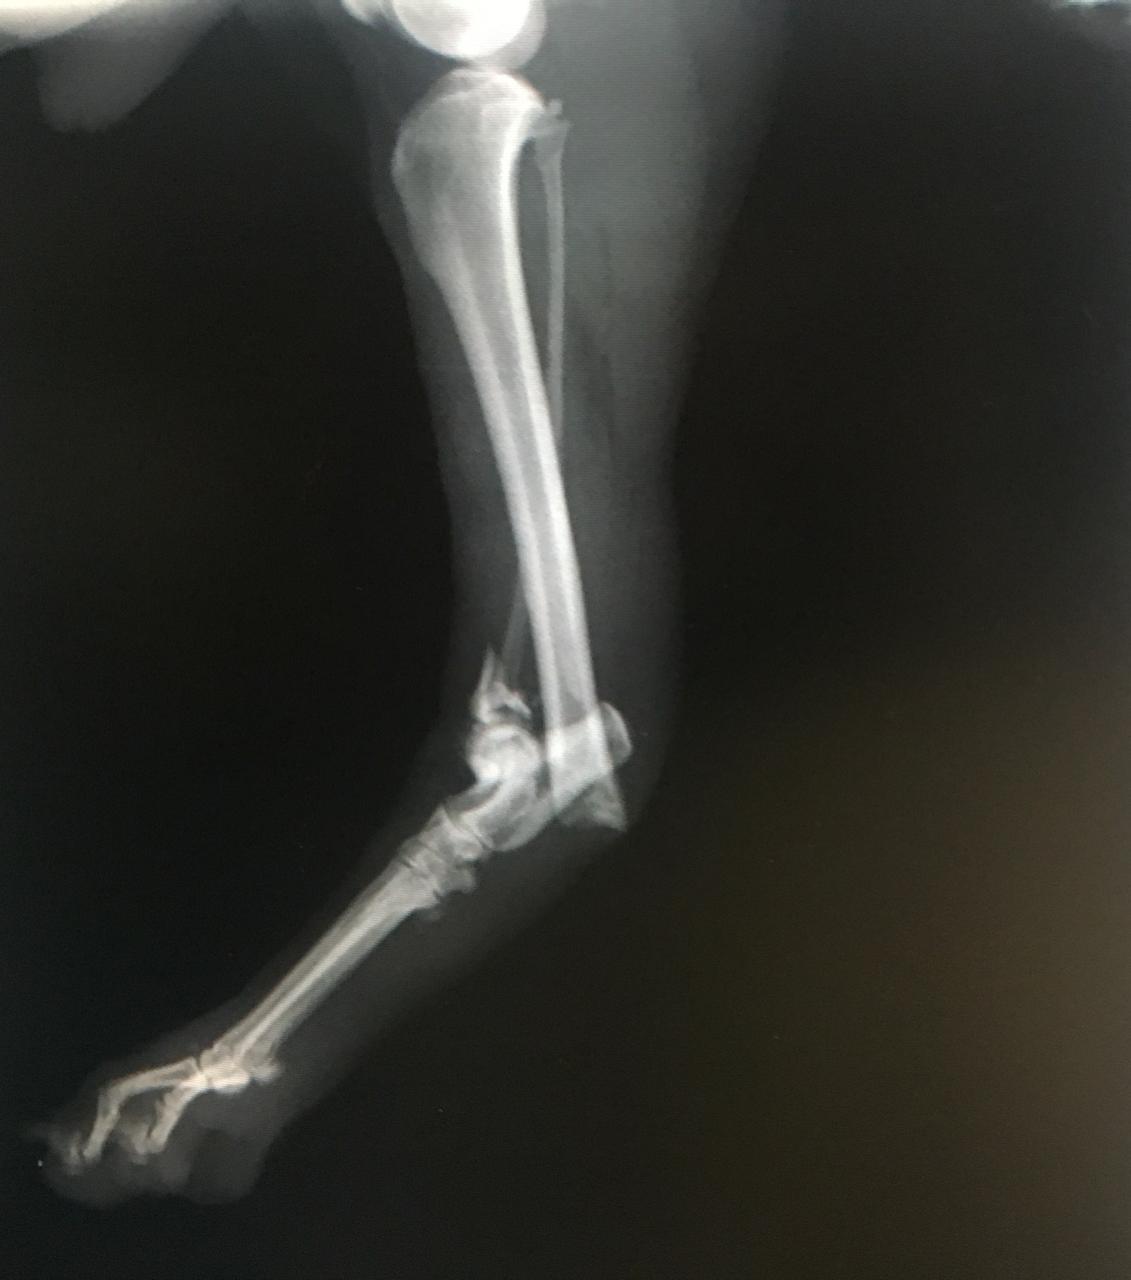

El Doctor Matias Montilla MP 163 especialista Traumatologo y ortopedista un ejemplo de lo que es brindarle importancia y seriedad a la medicina de animales de compañía y nos cuenta que en su clínica situada en capital (Mendoza 1771 norte ) incorporaron hace poco tiempo un maquina de última tecnología en radiología digital que es indispensable para el rápido diagnóstico en fracturas , malformaciones óseas, enfermedades Oncologicas óseas, y enfermedades articulares degenerativas, todas ellas son dolencias que cualquier mascota podría sufrir y podrías no saberlo.

El doctor nos explicó lo importante que es el rápido diagnóstico mediante Imagenes claras y revelado inmediato, este detalle puede salvarle la vida a tu mascota y evitar el sufrimiento. Por esto su visión de invertir en tecnología y educación continúa son sus principales objetivos.